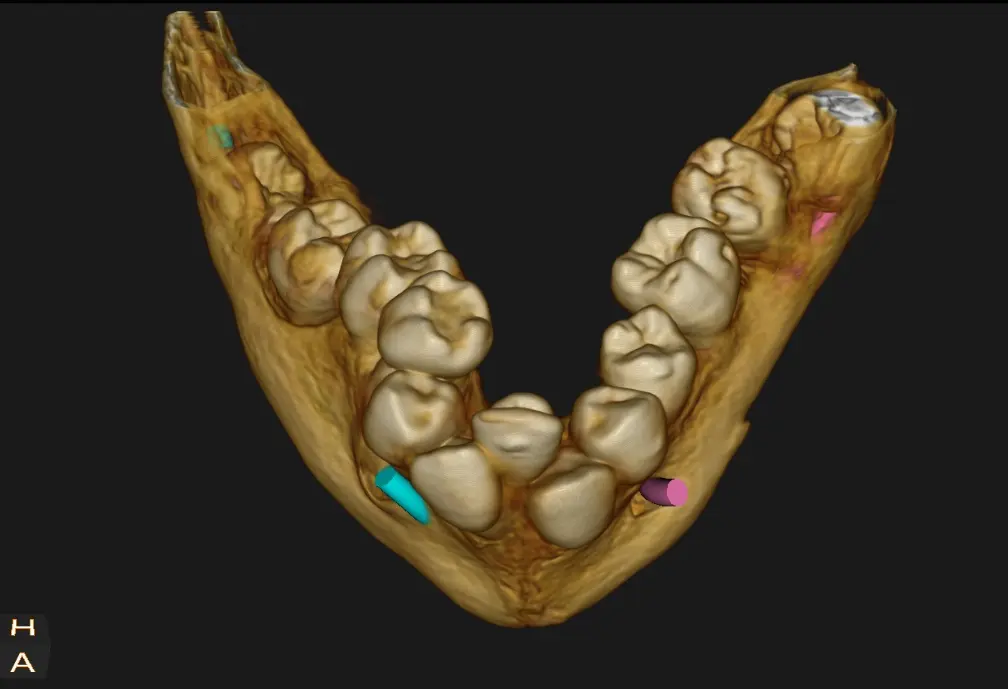

La paciente concurre a realizarse una telerradiografía de perfil con estudios cefalometricos para iniciar tratamiento de ortodoncia, 30 días después concurre nuevamente para realizarse una tomografía ya que la paciente relata que presenta el Síndrome de Pierre Robin, se logra observar un maxilar inferior de tamaño disminuido donde las piezas se encuentran apiñadas, el trastorno genera agenesia de los premolares en este caso piezas dentales 35 y 45 esta falta de espacio es una consecuencia común de la mandíbula pequeña (micrognatia).

La forma del arco en la imagen 3D permite visualizar esa imagen de arco en forma de "V"